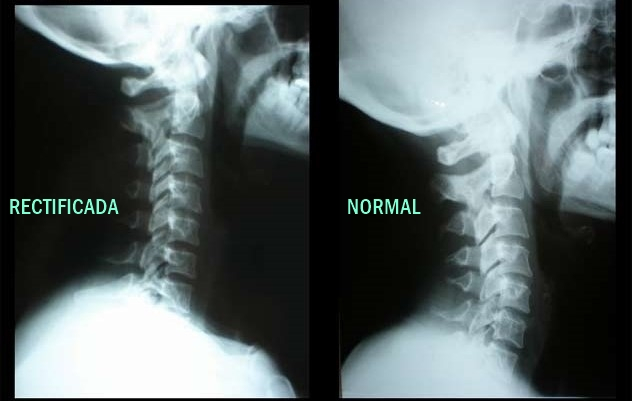

Se le llama lordosis cervical a la curvatura que se forma en la columna, específicamente hacia adelante. La columna está compuesta por las vértebras, las cuales (a pesar de que no lo parezca) no tienen una estructura recta. En realidad la columna está compuesta por dos curvas: lordosis y cifosis, las cuales diariamente se encargan de soportar todo el peso del cuerpo.

- La lordosis normal es cuando la columna cuenta con curvas.

- En cambio la hiperlordosis se produce cuando las curvas de la columna se acentúan más de lo normal. La hiperlordosis lumbar suele ser bastante dolorosa.

- Por otro lado la rectificación lumbar es la pérdida de las curvas normales de la columna. Como resultado de esto la persona afectada puede sentir mucho dolor o tener una postura arqueada. Esta afección suele ser bastante común durante el embarazo o al padecer problemas de sobrepeso.

- La inversión de arco cervical se produce cuando la rectificación lumbar evoluciona.